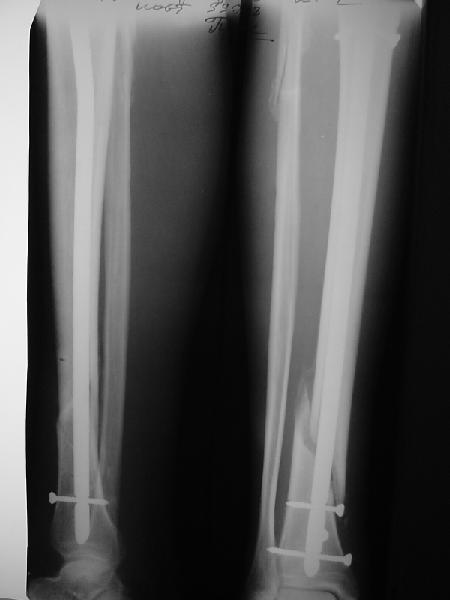

JOM> Кстати, если можно пошлите послеоперационный снимок.

Ok. А также и следующий, в 3 месяца.

Это наглядная демонстрация возможности ранней полной нагрузки при нестабильном по оси повреждении, причем не в самых благоприятных механических условиях - при плохом сопоставлении, со слабым фиксатором.

Сверху - один статический винт, а снизу - три. Что раньше сломается? Конечно, он потом и нижние сломал, и Вы правы, если бы верхний динамичесий винт уже уперся бы в нижний край отверстия, будь гвоздь подлинее, перфорировал бы сустав как пить дать.

Как я уже говорил, мы сделали выводы из этого и других подобных случаев. Очевидно, решений проблемы два - либо уменьшить нагрузку, либо увеличить прочность фиксатора. Первое решение работает не со всеми больными, так что пошли по второму пути - мы больше не используем гвозди с запирающими винтами диаметром 4 мм.